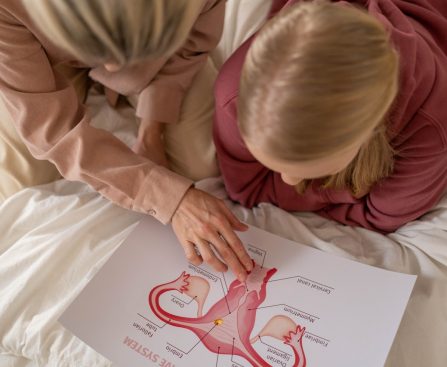

OVERVIEW Polycystic ovary syndrome (PCOS) is a problem with hormones that happens during the reproductive years. If you have PCOS, you may not have periods very often. Or you may have periods that last many days. You may also have too much of a hormone called androgen in your body. With PCOS, many small sacs of fluid […]

The vagina and the external structures of the vulva naturally range in shape, color, and size. There are no specific types of vagina, but each person’s vagina will have its own characteristics. When it comes to anything related to bodies and sexual and reproductive health, most people wonder, “Am I normal?” The answer regarding the […]